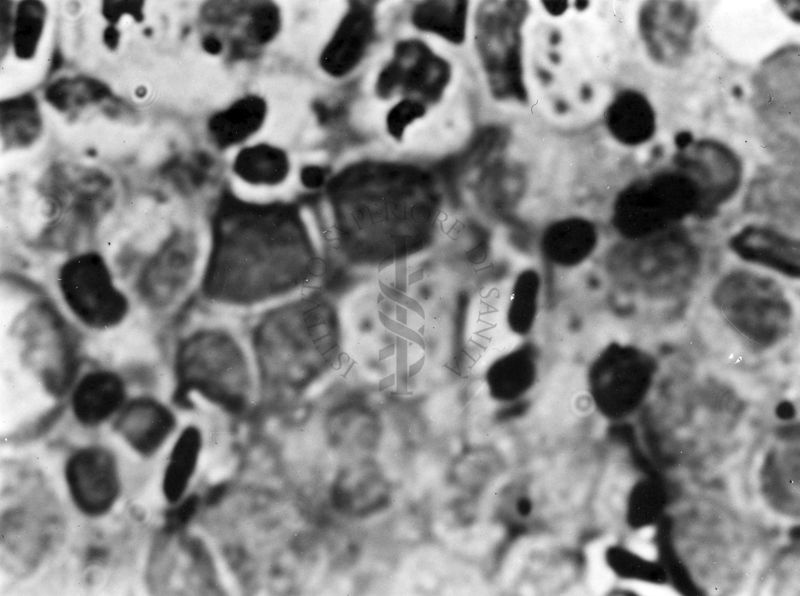

Fotografie di emoprotozoi